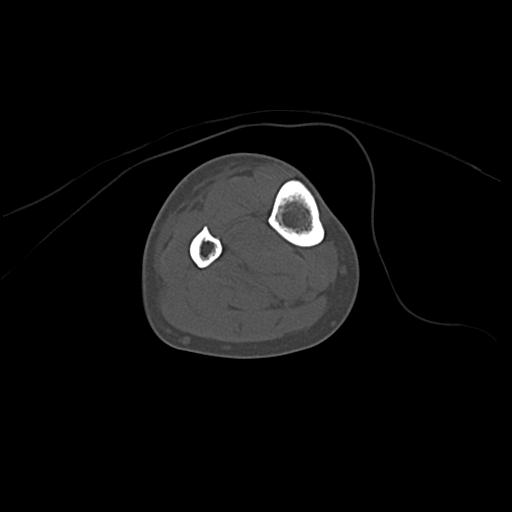

49554 3/13 膝 4R 3/16 4R 1/18 2R 78歳男性 膝蓋骨骨折